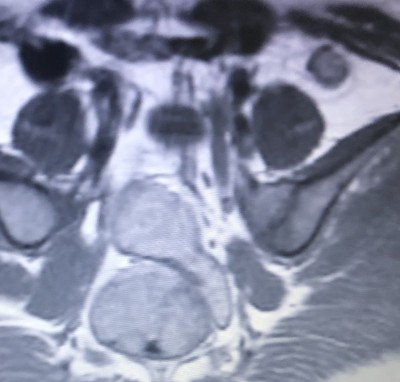

IlMerhaba arkadaşlar arkadaşım MR çekilmiş sonucu göstermemiş daha ama acaba hamile mi çok merak ediyoruz hamile gibi gözüküyor sizce image

Embriyo oluşmuş gibi görüyorum ama yanlış değilse. Ve hamilelik şüphesi varsa nasıl mr çekiliyor

Aynen bende öyle gördüm ama arkadaşımın beta hcg düşük çıkıyor 1.20 çıkıyor